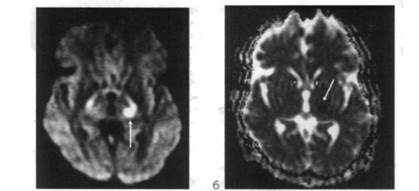

Диагностика ЛИ мозга возможна с учетом особенностей развития и течения заболевания, характера неврологических нарушений, которые воз­никают на фоне артериальной гипертензии. Однако неврологические син­дромы не всегда являются клиническим проявлением ЛИ мозга. Они могут быть обусловлены микрогеморрагиями, другими процессами несосудисто­го генеза (опухоли, воспалительные процессы, демиелинизация). Поэтому решающее значение для установления диагноза имеет визуализация лакун методами КТ, МРТ и диффузионно взвешенной МРТ (рис. 110). Мелкие лакуны размером до нескольких кубических миллиметров, которые вызывают развитие определенного неврологического дефицита, не всегда можно визуализировать даже с помощью рентгенорадиологических методов исследования. В случае лакунарного статуса методы КТ и МРТ в Т2-режиме позволяют обнаружить специфический феномен лейкоареозис, который характеризуется очаговой и диффузной демиелинизацией белого вещества вокруг желудочков мозга и в полуовальном центре.

МРТ головного мозга через 60 ч от начала инсульта (Т2-взвешенное изображение, аксиальная плоскость, срез на уровне глубоких отделов полушарий большого мозга): гиперинтенсивный яркий очаг (показан стрелкой) свидетельствует о лакунарном инфаркте в таламусе слева (клинически чисто сенсорный инфаркт)

Диффузионно-взвешенная томограмма головного мозга через 60 ч от начала инсульта: а - в ДВ-изображении (аксиальная плоскость) определяется гиперинтенсивный яркий очаг в таламусе слева (показан стрелкой), что подтверждает диагноз лакунарного инфар­кта; б - на карте диффузии выявлен гипоинтенсивный темный очаг инфаркта в таламусе слева (показан стрелкой) со сниженным коэффициентом диффузии